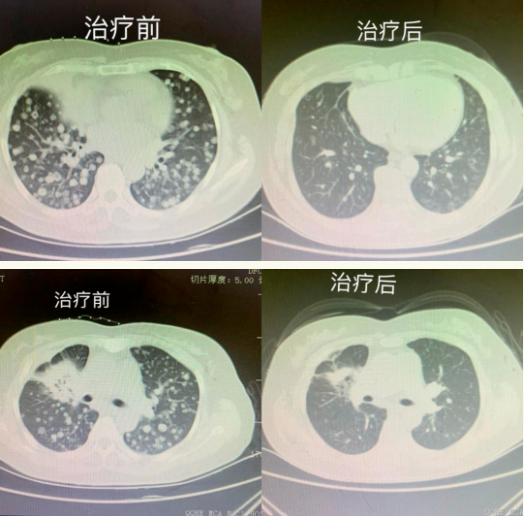

治疗前后对比

我们可以看到,该患者满肺的转移病灶几乎清除殆尽,脑转移病灶缩小明显,大部分已经消失。